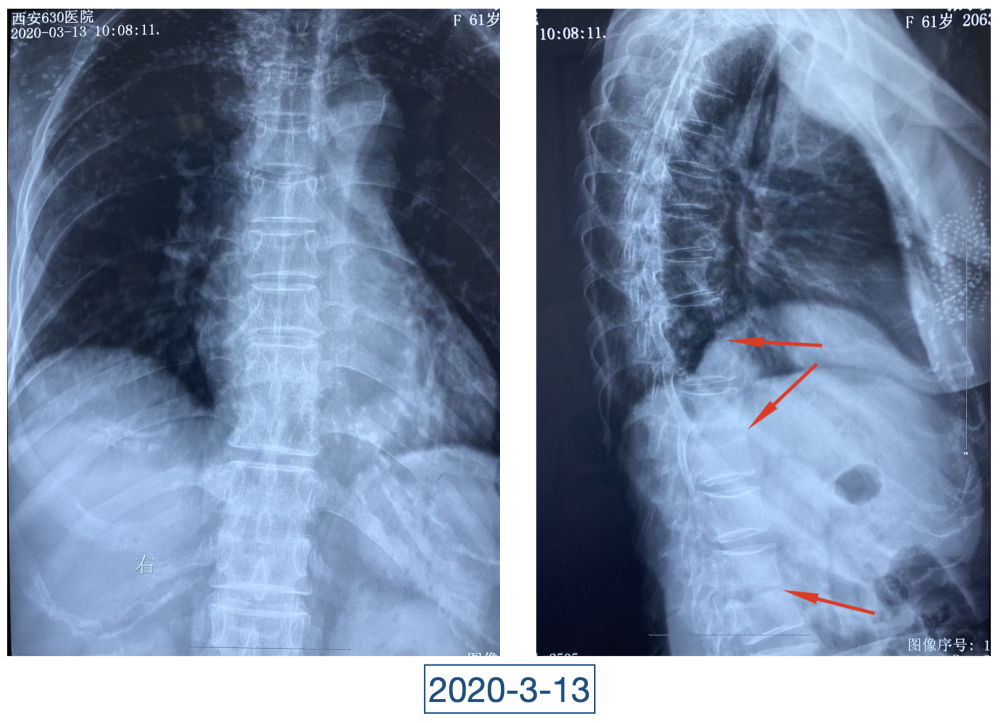

“虽说没到奄奄一息的地步,但一看就是患了大病,整个人都瘦脱相了。”李辉是西安市红会医院关节病医院病区副主任,2020年4月初第一次见到黄大娘时,他吓了一跳。黄大娘今年61岁,2019年腊月二十九,在家打扫卫生准备迎接新年的她突然开始高烧不退,腰背也痛。连夜送到当地医院补液、止疼、退烧、抗感染,一套组合拳下来烧是退了,疼痛的症状却持续在加重。从过年到正月,一直在当地医院输液、打针,黄大娘都没有好转,疼痛的地方反而越来越多。大概过半月,就多一个地方,腰、背、胸、颈部、关节、脚……此起彼伏,全身上下都觉得疼痛无比。哪里疼就去哪个科,今年四月前,黄大娘辗转多家医院多个科室寻求治疗,住院出院了一次又一次,连最高级别的抗生素都用到了,但就是没有效果。

全身上下11处骨关节被破坏!密密麻麻的诊断看得李辉毫无思绪,这么久都查不出来的病因能让他查出来吗?一时间,他也说不出话。看着黄大娘深深凹陷的双眼,浑身上下几乎看不见肉,就像罩着一层饥饿的青黄色的薄皮。过了好一会儿,他叹了口气,说:“先住下吧,用药把关节疼痛缓解一下,再想办法。”

经过科室讨论、会诊,李辉也查阅了很多资料,按照黄大娘的症状,他跟之前的接诊医生一样,觉得应该是骨关节感染。可之前的穿刺、培养各种检查也做过,为什么没有找到致病菌?李辉想,或许是检查中出现了问题,没有查对地方。于是他决定,在B超引导下骨穿刺,通过最新技术精准定位病灶,只有这样也许才能抓到真正的“罪犯”。

近日随访得知黄大娘身体好转,李辉脸上的笑容掩饰不住,他说,据查阅文献,11处感染灶,这是全世界感染灶最多的骨关节感染,但现在,这罕见、复杂的病已经被治愈。